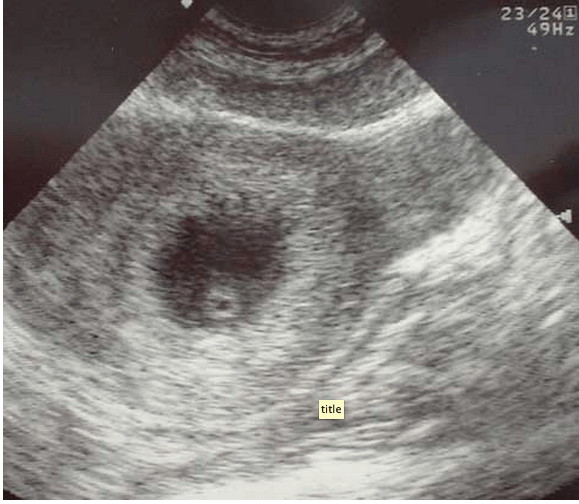

“You arrive to the emergency department for your first night shift of the month, and as you place your bag on the desk, the attending walks towards you with a chart in his hand. “Do you mind seeing this patient? It’s a COPD’er with dyspnea. It’s probably just a COPD exacerbation.” You look at the chart and see that it’s a 46 year old female with shortness of breath. As you walk into the room, you notice the patient appears slightly pale, is afebrile, has an O2 saturation of 91% and is tachycardic in the 110’s with a blood pressure of 105/76, temperature of 98.5° and respiratory rate of 26. While taking the history, you note that the patient is a smoker and recently returned from a 12 hour car ride to see relatives. Suspecting that this may be something other than simple COPD exacerbation, you grab your ultrasound machine and start with the cardiac echo (as described in the RADiUS protocol) and are able to get the following image:

This apical 4-chamber view shows severe right heart dilation, defined as a RV:LV ratio >1. However, you remember that the patient has a history of COPD, and chronic pulmonary hypertension can cause chronic right ventricular dilation1. At that moment, the patient becomes hypotensive with a systolic blood pressure in the 70’s and develops severe respiratory distress. What should we do?